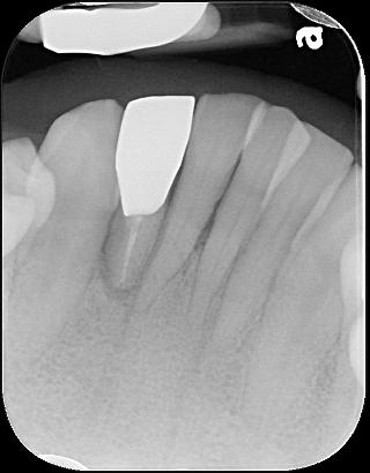

本病患為嚴重蛀牙,導致牙齒斷裂,經評估,骨頭良好,因此可拔牙後立即植牙,減少等待時間,待植體癒合後,再進行膺復處置

拔牙、立即植牙、補骨